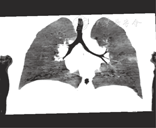

患儿,男,20个月,咳喘1 d,加重半天入院。查体:T 36.5 ℃,P 120次/min,R 56次/min,神志清楚,呼吸急促,口周微绀,可见鼻扇及三凹征,双侧胸廓对称,呼吸运动一致,听诊双肺呼吸音对称,闻及大量喘鸣音,叩诊呈清音。心音有力,律齐,心率120次/min,各瓣膜区未闻及病理性杂音。既往史:自生后7个月开始有4次反复咳喘史,胸片均提示支气管肺炎,给予抗感染及对症治疗后病情有所好转。此次入院辅助检查:胸片提示左肺可见少许斑片影,血气分析:pH 7.35,PCO2 48 mmHg(1 mmHg=0.133 kPa),PO2 40 mmHg,Lac 0.3 mmol/L,BE -5 mmol/L,K+ 3.6 mmol/L,Ca2+ 1.18 mmol/L,GLU 4.3 mmol/L,Na+ 143 mmol/L。初步诊断:肺炎,Ⅰ型呼吸衰竭。经吸氧,抗感染,保持气道通畅,平喘化痰等对症治疗后效果不佳,咳喘重,故进一步完善多层螺旋CT检查(图1、图2),提示右上叶支气管下方见异常分支支气管,供应右上叶肺段,余左右支气管管腔通畅,未见狭窄及阻塞。临床诊断:气管性支气管(额外型)。

多层螺旋CT操作快,无创伤及痛苦,没有并发症,其呼吸道的三维重建成为诊断气管性支气管最佳检查方法,文献报道其检出率明显高于支气管内镜[3],它可以明确诊断及分型,还可以进一步了解气管狭窄的位置和程度,为临床诊断提供了依据。本文报道的患儿属于额外型,未发现其他先天发育异常。